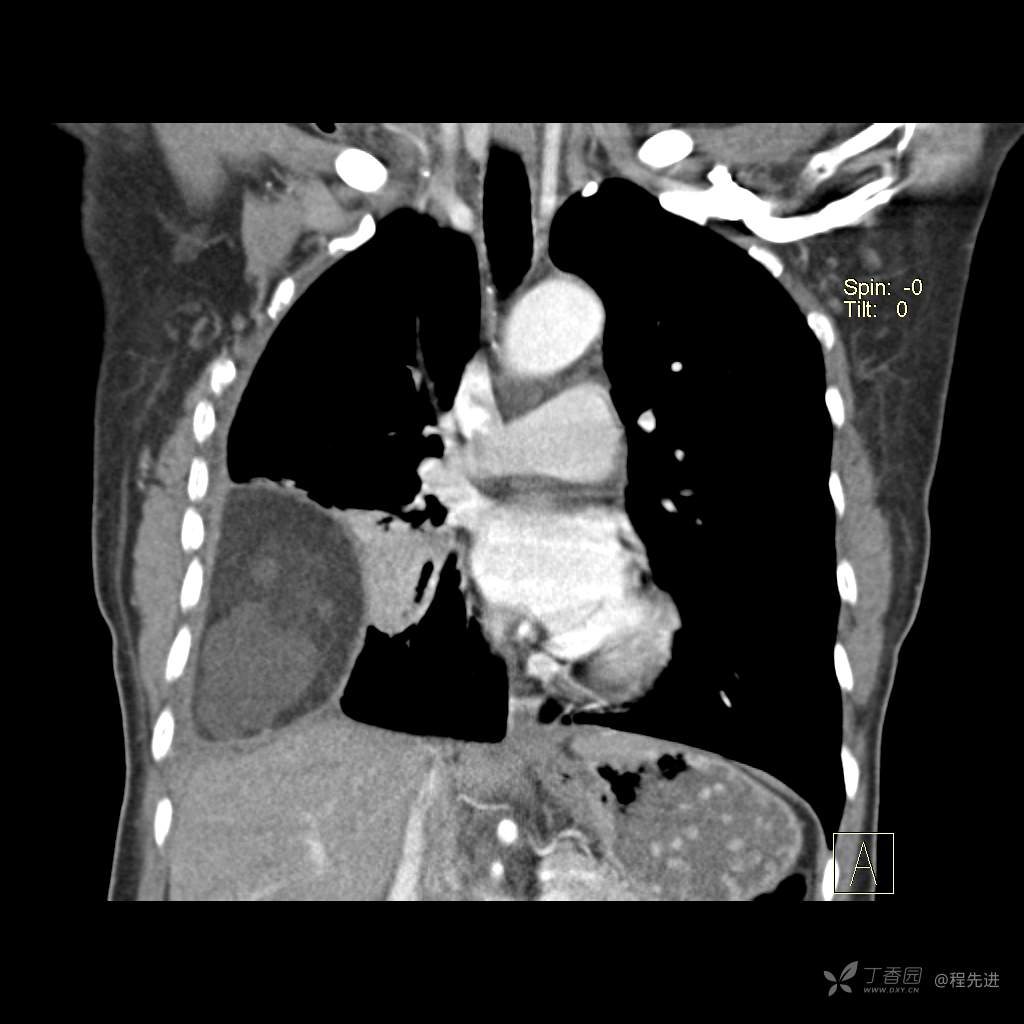

患者性别:女

患者年龄:51岁

简要病史:胸闷半年